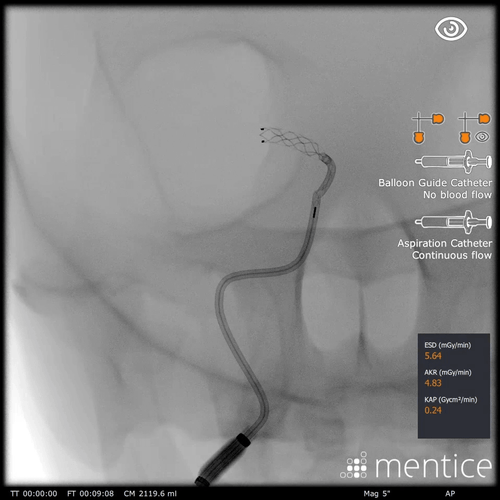

Our anatomical software physics engine, combined with haptic-enabled hardware solutions, creates the optimal environment for procedural adoption, proficiency-based training, patient-specific simulation, and objective skills assessment. Over 350 development years of engineering have created the most advanced IGIT simulation solutions on the market.

Over 2000+ systems delivered worldwide that cover fluoro & echo based learning solutions from head to toe for both Healthcare Professionals and the MedTech Industry.